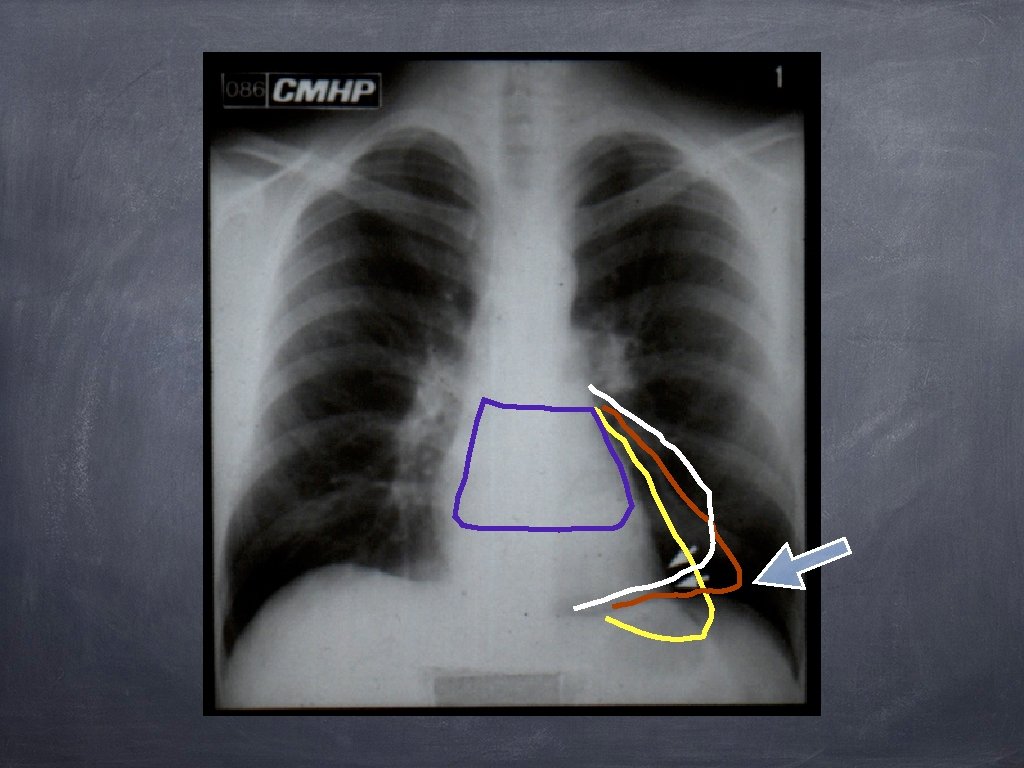

CARACTERELE GENERALE OPACITAȚILOR MEDIASTINALE LIMITA EXTERNA NETĂ ȘI CONTINUĂ FORMA CONVEXĂ SPRE PLAM N RACORD ÎN PANTĂ LINĂ CU MEDIASTINUL LIMITA INTERNĂ NEDELIMITABILĂ (SILUETAJ)

Semiologia opacităților mediastinale DEPLASĂRI ALE LINIILOR MEDIASTINALE; SEMNUL SILUETEI; SEMNUL CERVICO-TORACIC; SEMNUL CONVERGENȚEI HILULUI; SEMNUL ACOPERIRII HILULUI; SEMNUL “ICEBERG” – ului; SEMNUL ATRACȚIEI ESOFAGULUI

Semnul convergenței hilare